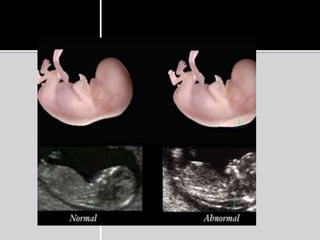

2.Gestational sac features

 Abnormal size :

Nyberg et al refined the definition of an

abnormal gestational sac as MSD of 25.0mm

or more without an embryo, or MSD of 20.0

mm or more without a yolk sac.

 Other features include :

• Distorted GS shape

• Thin trophoblastic reaction

• Weakly echogenic trophoblast

• Abnormally low position of the GS within the

endometrial cavity.